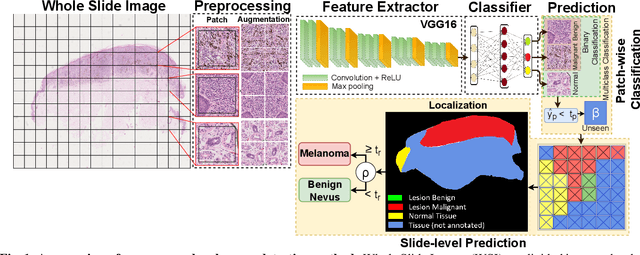

Melanoma diagnosed and treated in its early stages can increase the survival rate. A projected increase in skin cancer incidents and a dearth of dermatopathologists have emphasized the need for computational pathology (CPATH) systems. CPATH systems with deep learning (DL) models have the potential to identify the presence of melanoma by exploiting underlying morphological and cellular features. This paper proposes a DL method to detect melanoma and distinguish between normal skin and benign/malignant melanocytic lesions in Whole Slide Images (WSI). Our method detects lesions with high accuracy and localizes them on a WSI to identify potential regions of interest for pathologists. Interestingly, our DL method relies on using a single CNN network to create localization maps first and use them to perform slide-level predictions to determine patients who have melanoma. Our best model provides favorable patch-wise classification results with a 0.992 F1 score and 0.99 sensitivity on unseen data.